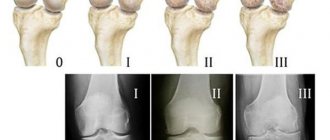

показания к приему терафлекс адванс

Дегенеративно-дистрофические суставные патологии характеризуются хроническим течением. При их продолжительном лечении немаловажно, чтобы применяемые медикаменты